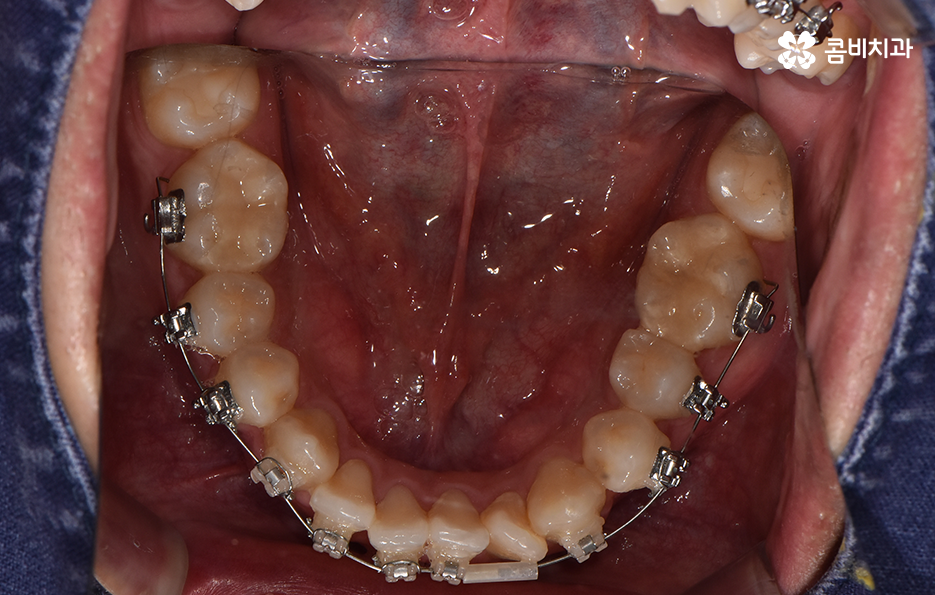

오늘 포스팅에서 보여지는 사진에서는 비발치 교정으로 덧니 교정이 가능했던 사례입니다. 덧니 교정 사례에서 발치교정 케이스는 흔한 치료 방법이긴 하지만 발치에 대한 판단은 치열만이 아니라 골격과 얼굴형을 종합적으로 고려하여 판단하고 치아를 얼마나 이동시켜야 할지 예측하여 판단하기 때문에 3D CT 등의 첨단 장비를 통한 검진과 경험 많은 교정 전문의와 충분히 상의하고 결정해야 합니다

종합하면 발치교정의 필요성은 얼굴과의 조화, 골격 그리고 교합 등을 전체적으로 고려하여 판단하기 때문에 각 환자분들이 필요한 치아의 이동 정도를 정확히 예측하고 필요한 치아 이동 공간을 확보함에 있어서 발치교정이 적합할지 아니면 비발치적인 방법으로도 치아 이동 공간이 확보 가능한지 따져보고 있으며 발치교정이 아니더라도 치간삭제, 악궁확장, 어금니 후방이동과 같은 방법으로 공간 확보가 가능하기 때문에 각 환자분들에게 적합한 1:1 맞춤형 치료가 진행되고 있어요